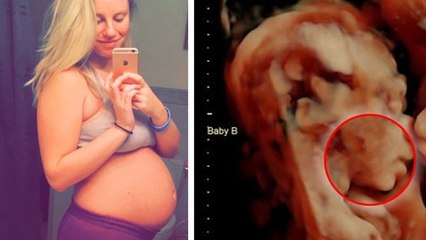

Cette future maman de 23 ans pensait qu'elle attendait des jumeaux. Mais quand elle a vu l'échographie...ça a été le choc !